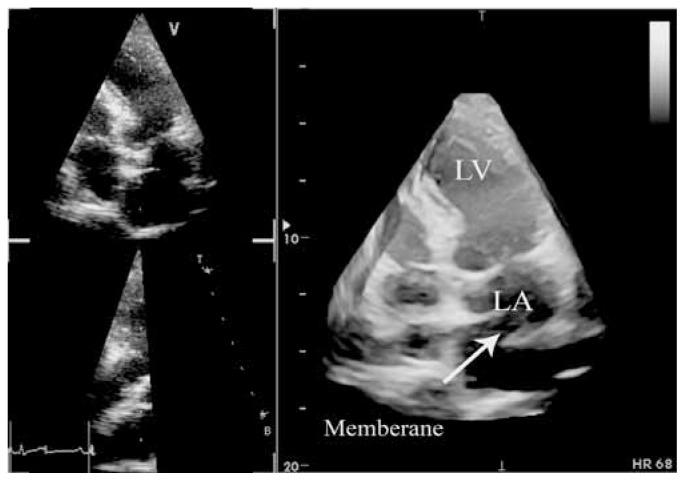

Cor triatriatum sinistrum is a rare congenital cardiac malformation, accounting for about 0.1-0.4% of all congenital heart diseases and characterized by the presence of a fibromuscular membrane that subdivides the left atrium into two chambers in the classical form. While classic cor triatriatum in most patients can be observed during the neonatal period or early infancy, it is very rare in adults.We herein present an incidental finding of cor triatriatum sinistrum in a middle-aged man with coronary artery disease scheduled for coronary artery bypass graft surgery. The patient was admitted for exertional dyspnea and chest pain of a three-month duration. He had a past medical history of mild hyperlipidemia and mild hypertension. Transthoracic two-D echocardiography (TTE) demonstrated a visible presence of a membranous band in the mid portion of the left atrium with obvious obstruction by color and Doppler flow measurements, confirmed by three-D echocardiography. Selective coronary angiography also revealed a severe ostioproximal stenosis of the left anterior descending artery of up to 99%.On-pump coronary artery bypass grafting was performed without complications, during which the anastomosis of the left internal mammary artery to the left anterior descending artery and the removal of the membrane were done.

左房三房心是一种罕见的先天性心脏畸形,约占所有先天性心脏病的0.1 - 0.4%,其典型表现为存在一个纤维肌性隔膜,将左心房分为两个腔室。虽然大多数患者的典型三房心在新生儿期或婴儿早期即可观察到,但在成人中非常罕见。我们在此报告一例在计划进行冠状动脉搭桥手术的中年冠心病男性患者中偶然发现的左房三房心病例。该患者因持续三个月的劳力性呼吸困难和胸痛入院。他有轻度高脂血症和轻度高血压病史。经胸二维超声心动图(TTE)显示左心房中部可见一条膜状带,通过彩色和多普勒血流测量显示有明显梗阻,三维超声心动图证实了这一点。选择性冠状动脉造影还显示左前降支近端严重狭窄达99%。在体外循环下进行冠状动脉搭桥手术,无并发症发生,术中完成了左乳内动脉与左前降支的吻合以及隔膜切除。